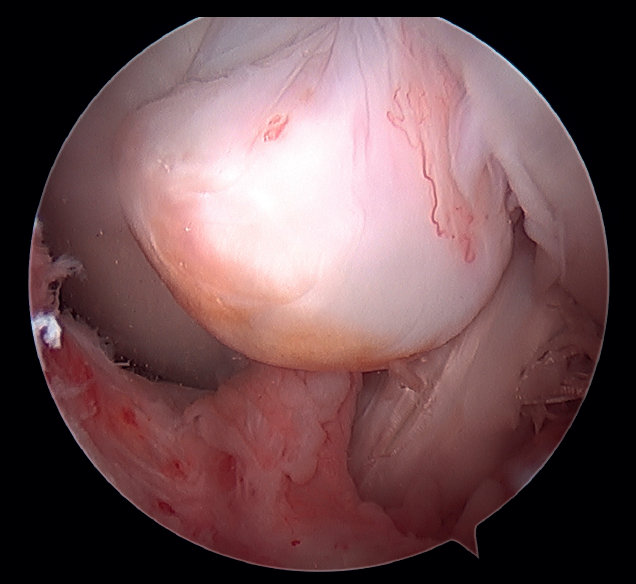

Knee arthroscopy in which an inverted cyclops lesion is observed. Cyclops lesion consists of a fibrous nodule that forms at the central pivot of the knee following surgeries with an intraarticular approach. The incidence ranges between 1-10% of all knees subjected to anterior cruciate ligament (ACL) ligamentoplasty, though the condition is not always symptomatic. Its most common location is at the tibial origin of the ACL. Only 5 cases involving a femoral origin, as in our case, have been reported in the literature to date.